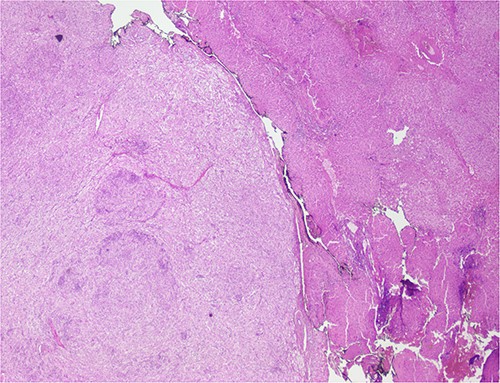

The histological evaluation of the surgical specimen revealed a storiform fusiform cell neoplasm with expansive borders, areas of a myopericytomatous pattern, and the presence of rhabdoid cells (Fig. 4). The neoplastic cells, spindled to oval, with eosinophilic and granular cytoplasm and with mild nuclear atypia, were organized in small bundles (Fig. 5). Anomalous arterial structures were observed. Neither necrosis nor mitotic figures were identified. The immunohistochemical study revealed immunoreactivity of neoplastic cells for SMA, HHF35 (Fig. 6) and HMB45 (Fig. 7), Calponin, S100 and CD31. The margins did not intersect the neoplasm. Thus, contrary to the preoperative diagnosis of hepatocellular carcinoma, the morphological aspects and the immunohistochemical profile favored the diagnosis of epithelioid angiomyolipoma.

Liver parenchyma partially occupied by a neoplastic proliferation with expansive borders.